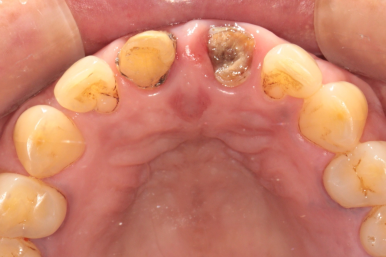

앞니 보철물이 빠져서 내원하시게 되신 환자분의 케이스입니다.

타원에서 치료받으신 보철물을 그동안 잘 사용하고 있었는데,

어제 갑자기 윗니 쪽으로 가벼운 충격이 있었고,

바로 보철물이 빠지셨다고 합니다.

2024. 1 기존의 보철물은 위 앞니 두 개를 연결한 형태였다고 하시네요.

환자분의 현재 상태를 보고 원인을 유추해 보았습니다.

기존에 연결된 앞니 보철물과 치아의 경계부 사이로 2차 충치가 진행이 오랜 기간 지속되었고,

보철물 내부의 치아에 충치가 심해져 약해져 있던 상태에서

작은 충격에 그 보철물이 빠져버리게 된 것입니다.